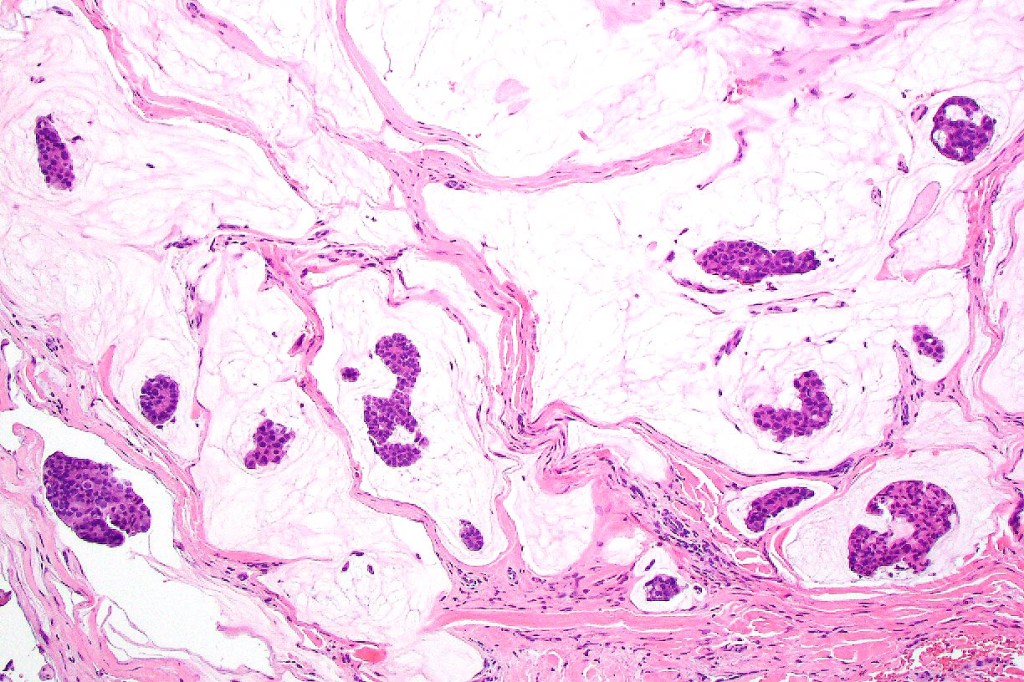

•Mucinous carcinoma is characterized by epithelial islands dispersed in a rich mucinous stroma

•DPAS, colloidal iron & Alcian blue ph 2.5 +ve

•Eosinophilic cytoplasm & small vesicular nuclei

•Mitoses scanty to absent

•No significant pleomorphism

•+/- in situ component